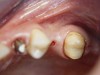

A 53-year-old female was referred for evaluation of a fracture of tooth No. 24. The tooth had been treated endodontically 5 years prior. The radiograph revealed a complete fracture of the tooth involving the crown (Figure 12). Tooth extraction and immediate placement of a an implant that was 10 mm in length and 3.75 in diameter was planned.

At the time of surgery, the tooth was extracted without harvesting any mucosal flap because the implant site was prepared by means of a pilot drill bur (Figure 13) and alternating osteotomes (Figure 14A and Figure 14B). The implant was positioned and showed primary stability. The implant was loaded 2 days after surgery. Then, splinted PFM crowns supported by custom gold abutments were delivered. At 6 months posttreatment, the radiograph revealed no bone resorption and the clinical result was optimal (Figure 15A and Figure 15B).

Figure 13  The drill bur was used to start the implant site preparation.

Figure 13